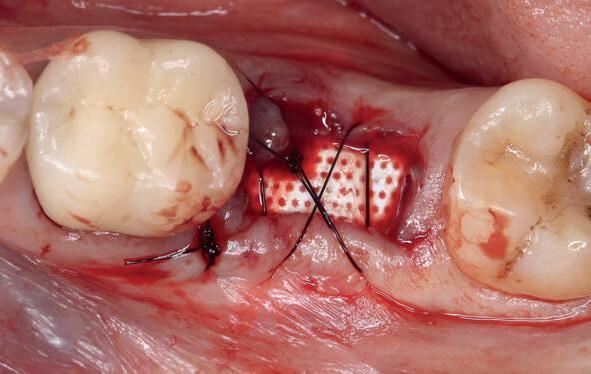

Er wordt besloten om botmateriaal te plaatsen in de extractie-alveole. Vervolgens wordt het afgesloten met een titanium versterkt d-PTFE membraan (afbeelding 2). Na vier weken wordt het membraan verwijderd.

Zes maanden na extractie wordt het implantaat 37 geplaatst. Er is sprake van een goede genezing en de processushoogte en -breedte zijn behouden en opgebouwd. Ook is er zichtbaar gekeratiniseerd weefsel

1 2 Ridge preservation met d-PTFE membranen 35

gewonnen. De wond kan na het plaatsen van een healing abutment primair gesloten worden (Afbeelding 3a-3d).